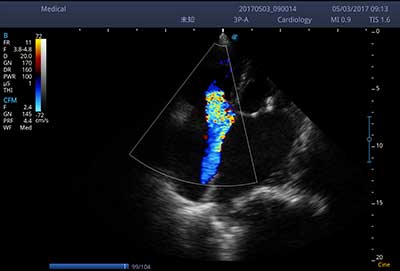

E3便携式彩色多普勒超声诊断系统拥有专业超声技术平台、高度集成化的硬件模块和结构设计、简便的操作流程、支持三探头接口全激活,兼顾了优质图像、轻便机身以及台便两用的临床使用需求。无论在常规超声科门诊检查,还是在急诊、麻醉、ICU、户外等各种应用场景。都能给您带来流程的操作体验。

频谱自动包络